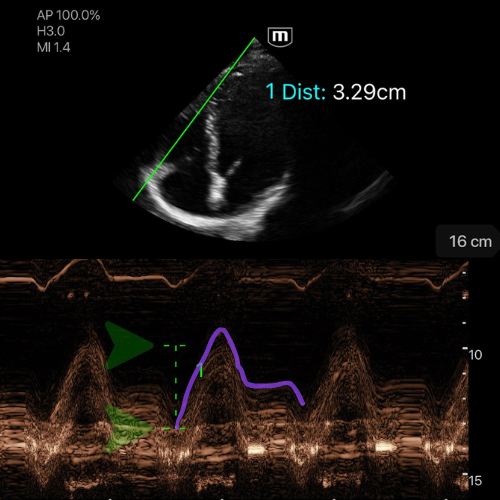

TAPSE (déplacement systolique de l’anneau tricuspide) : normal > 17 mm.

🖥 Vue : en A4C centrée sur le VD et l’anneau tricuspide latéral.

🎯 Alignement : le curseur en Mode M exactement sur l’anneau tricuspide latéral (jonction VD/oreillette droite, paroi libre).

📈 Lancement mode M : on active le mode M et on vérifie qu'il y a une courbe avec un mouvement net de va-et-vient de l’anneau (un pic systolique bien visible).

📏 Mesure : on mesure en millimètres la distance entre le point le plus bas en diastole et le point le plus haut en systole (amplitude du pic).

✅ Interprétation :

TAPSE ≥ 17 mm → fonction systolique du VD conservée

TAPSE 13-17 mm → dysfonction légère

TAPSE 10-13 mm → dysfonction modérée

TAPSE < 10 mm → dysfonction sévère

![]()